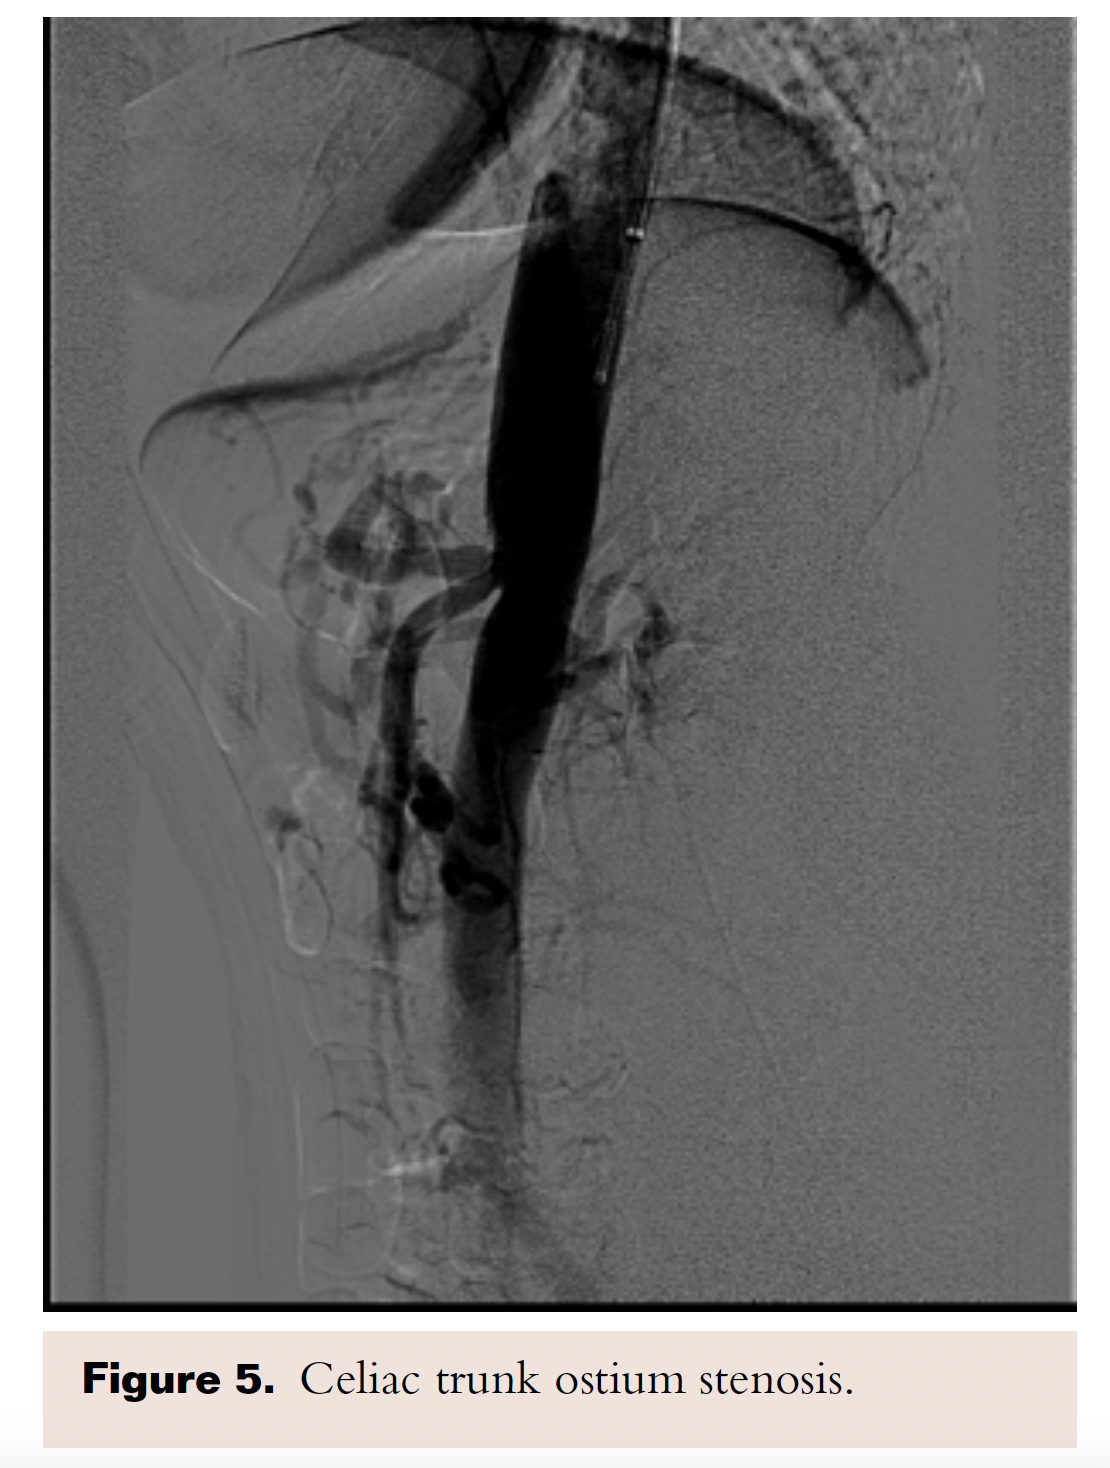

A discussion with the patient regarding treatment options was done, and considering her comorbidities and patient preference, the decision was made for minimally invasive endovascular stenting. A selective angiography of the celiac trunk was performed via the left brachial artery access using a 5 Fr, 125 cm, MP A-2 catheter (Merit Medical Systems, Inc) over the Supracore guidewire (Abbot Vascular). A 90% stenosis in the celiac trunk was identified, and SMA and IMA had no significant stenoses (Figure 5).